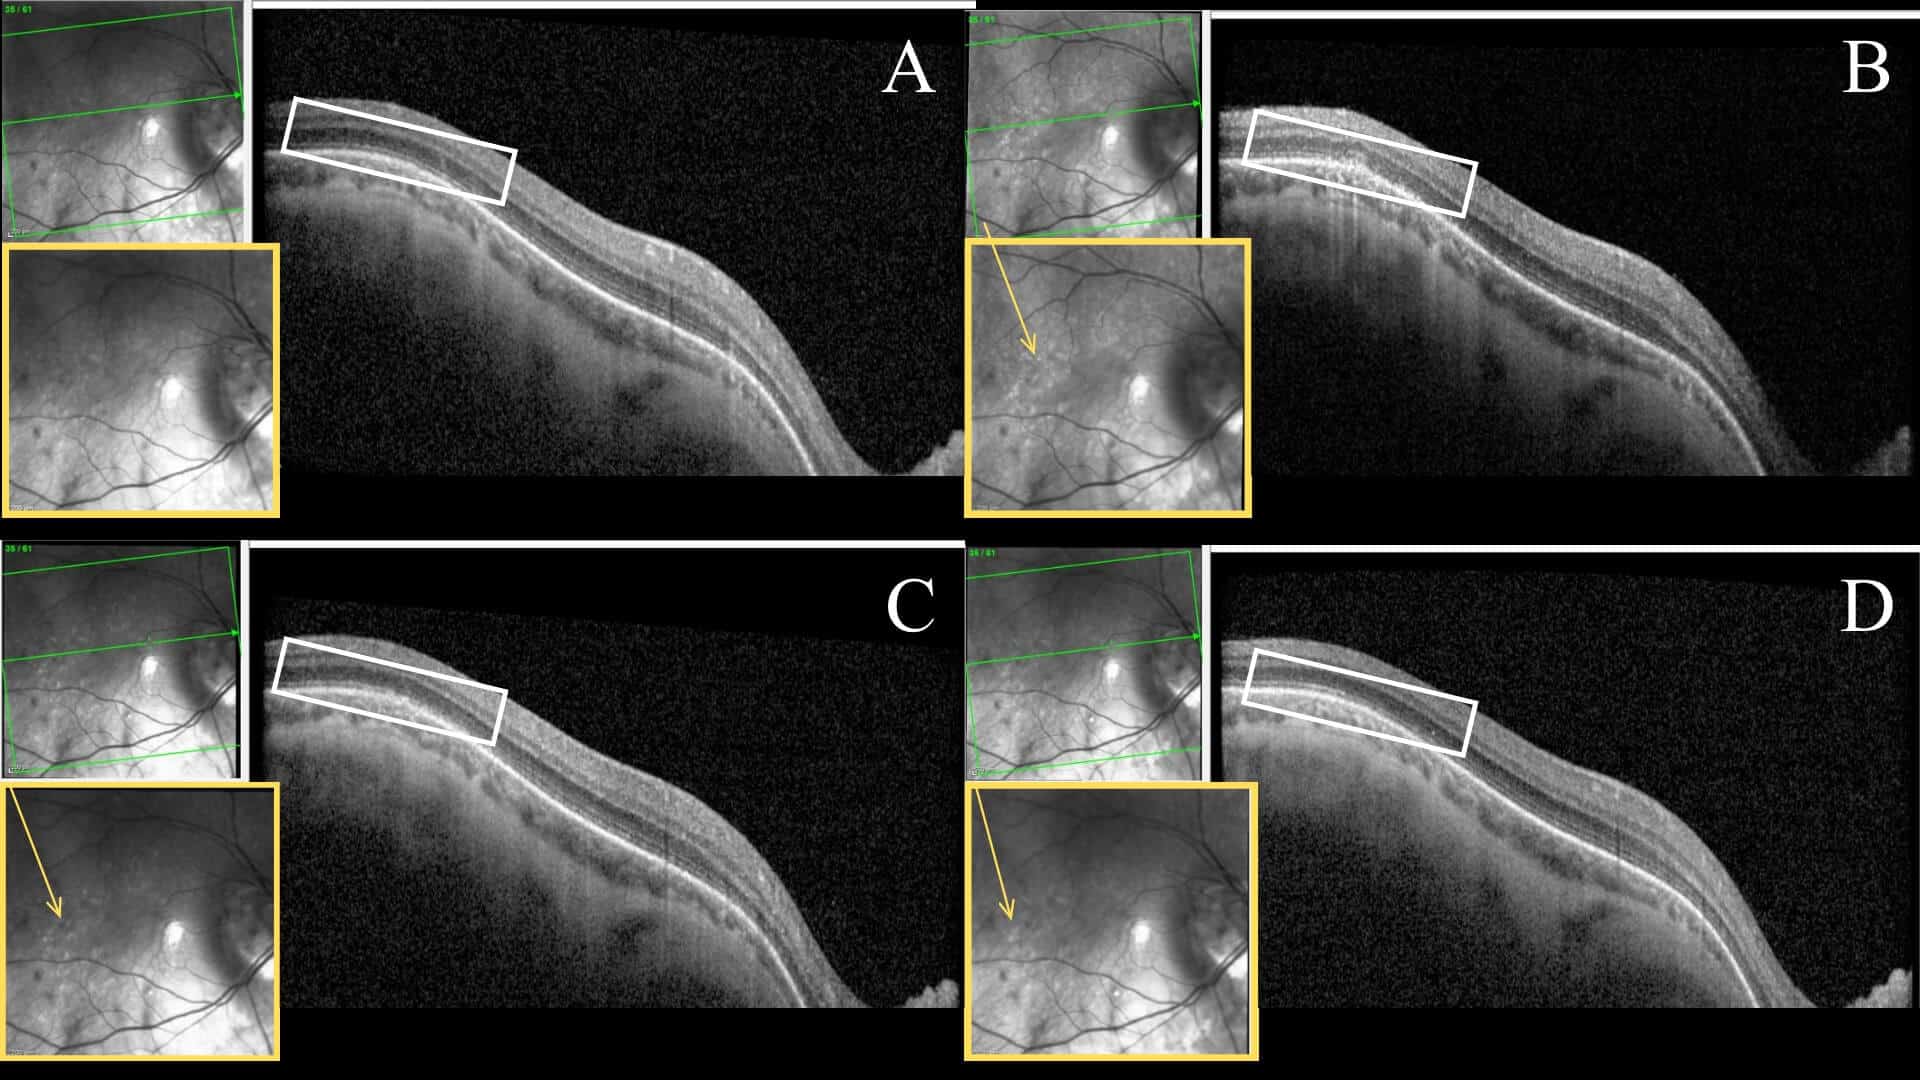

Figure 2: Serial SD-OCT images of the right eye at initial onset (A), one week (B), one month (C), 3 months (D). The white rectangle highlights retinal layers temporal to the fovea that undergo an apparent disruption with an eventual resolution at the EZ layer. The yellow box of each scan shows an enlarged infrared reflectance image. Within this imaging, hyperreflective lesions are visibly scattered throughout the posterior pole, highlighted by the yellow arrow.